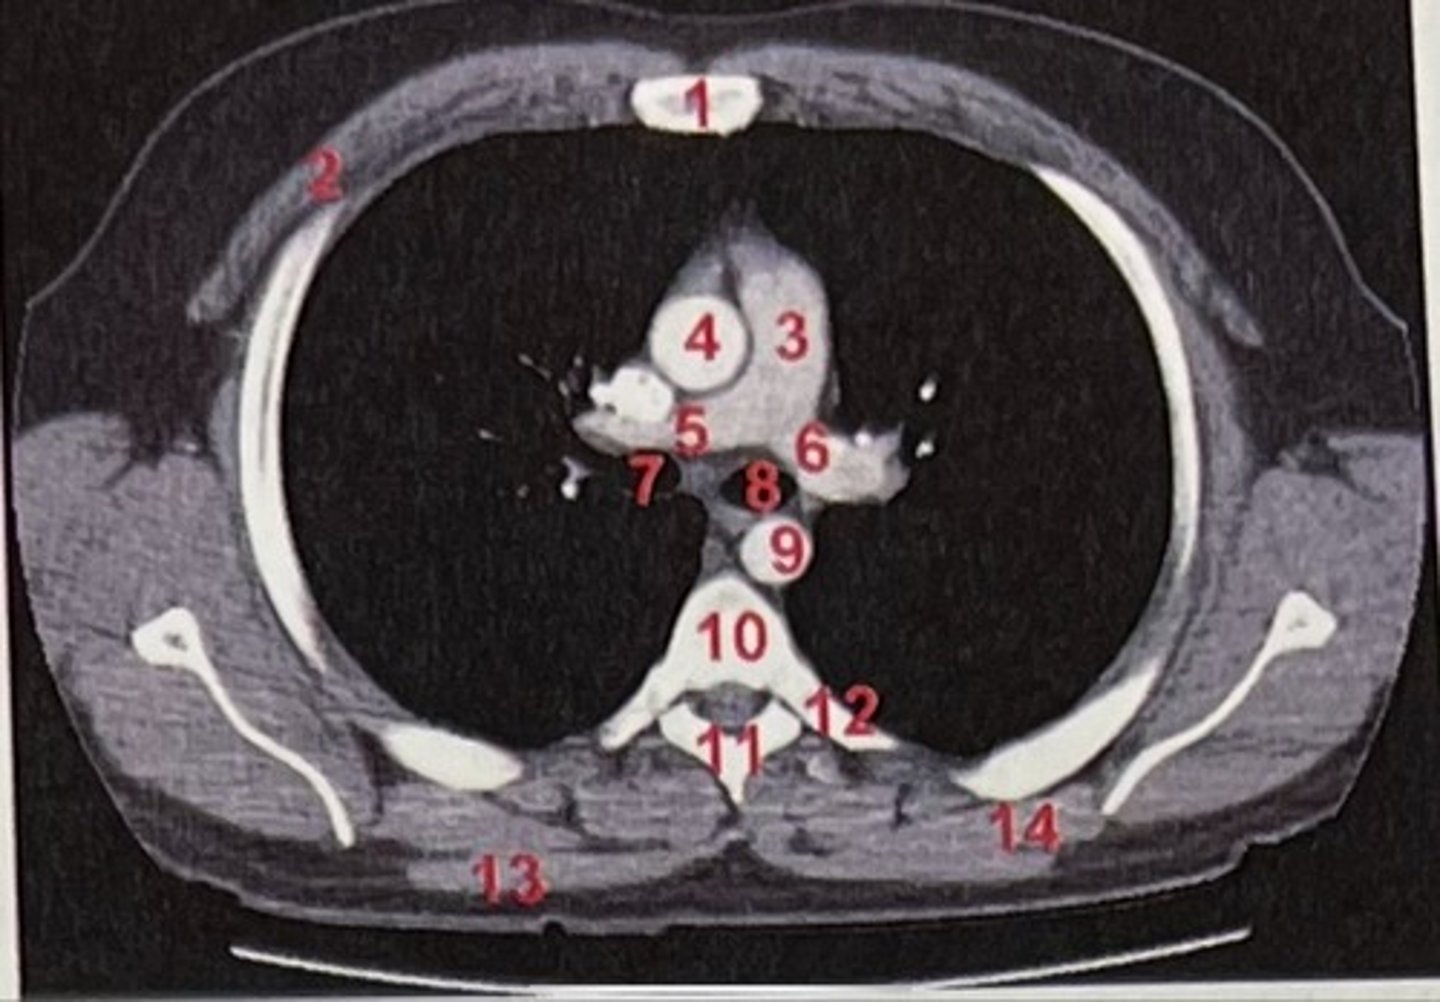

Sternum

What is 1

pectoralis major

What is 2

Pulmonary trunk

What is 3

Right and left pulmonary arteries

What is 5 and 6

Ascending aorta

What is 4

right primary bronchus, left primary bronchus

What is 7 and 8

Descending aorta

What is 9

Rhomboid major

What is 14